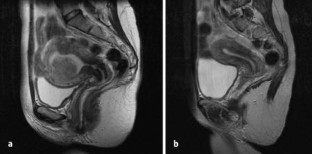

Abb. 1a,b

Abb. 5a,b